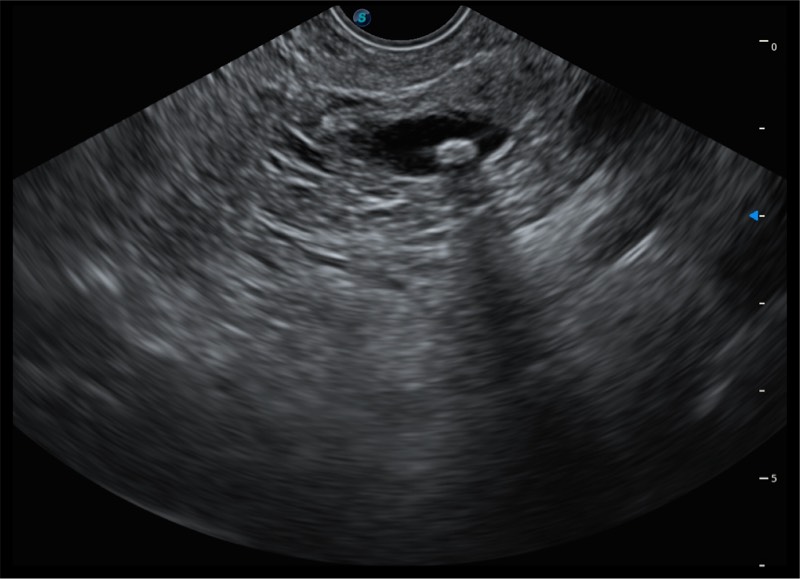

搭载百万级CMOS成像技术

及自主研发凸阵换能器,

可呈现优质的内镜和超声画面

基于二十年的超声技术积累,狗万官方网站提供了最新一代的独立超声主机,在提供高质量图像的同时满足多学科使用。具备常见多普勒技术并提供弹性成像、声学造影等高端影像技术。新一代传感器具有更强的抗干扰能力并减少图像伪影。